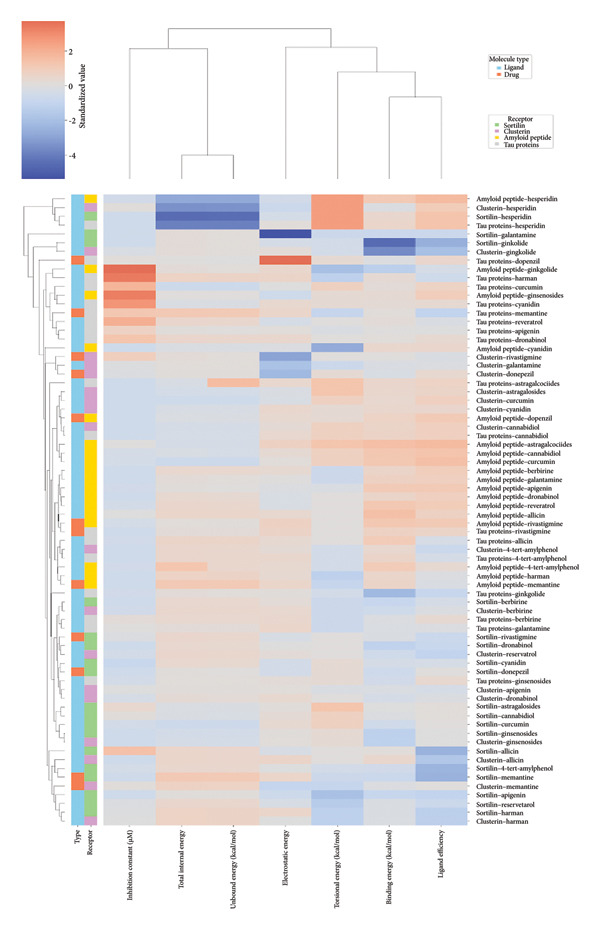

The heatmap in Figure 6 provides a comprehensive visual interpretation of the AutoDock Vina docking analysis of natural ligands (light blue‐coded) and reference drugs (orange‐coded) against four key AD‐related receptors. Ginkgolide consistently demonstrates strong (deep red coloration) binding energies across all four receptors: sortilin (blue‐coded), clusterin (green‐coded), Aβ peptide (yellow‐coded), and tau proteins (purple‐coded). Natural ligands exhibited varied yet significant binding profiles; ginsenosides showed strong affinities for tau proteins and Aβ peptide, with moderate binding to sortilin and clusterin. Dronabinol displayed particularly strong interactions with sortilin and Aβ peptide, while berberine and apigenin consistently showed favorable binding across multiple targets, underscoring their broad spectrum of action. In stark contrast, hesperidin consistently presented among the weakest binding affinities across most receptors (indicated by blue/lighter colors), suggesting limited direct molecular interaction.

Comparative analysis against the established reference drugs—memantine, donepezil, and rivastigmine—revealed that several natural compounds, most notably ginkgolide, achieved binding affinities that were superior to these therapeutic agents across various AD‐related targets, highlighting their significant potential as alternatives or adjuncts. The hierarchical clustering patterns displayed by the dendrograms provided further insights: Molecules grouped together along the y‐axis (ligand–receptor pairs) often shared similar overall binding characteristics. For example, ginkgolide consistently clustered within highly favorable binding groups across multiple receptors (Figure 7), and groups like ginsenosides and cyanidin showed similar strong binding patterns toward tau proteins. Notably, certain natural ligands, such as allicin and harman, clustered with other smaller, more drug‐like natural compounds. Importantly, this clustering also revealed instances where natural ligands exhibited similar binding profiles to reference drugs like memantine, donepezil, or rivastigmine, suggesting potentially shared binding modes or therapeutic mechanisms.